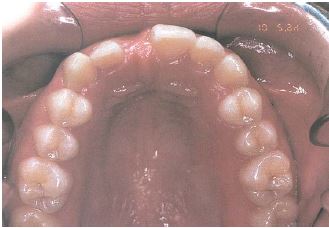

lahihambumus, kui kontaktis on ainult molaarid ehk tagahambad